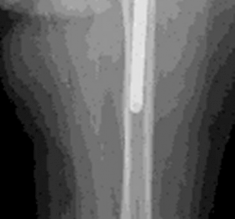

5. Diaphyseal Fixation for Severe Bone Loss (Paprosky Type IIIB/IV):

• For extensive diaphyseal bone loss (Paprosky Type IIIB) where proximal fixation is compromised, long, fully porous-coated stems are used to achieve stable fixation in the distal diaphysis, bypassing the defects. These stems may be tapered or cylindrical.

• For Type IV defects or those requiring extensive cortical reconstruction, custom stems or allograft-prosthesis composites may be necessary.